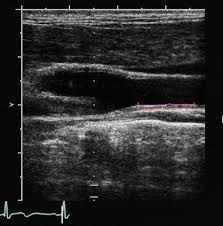

Portable Sonogram Machine Portable Ultrasound Scanner with Multi-frequency Probes

| 6. | High quality clinical image | Image quality is more beautiful and distinctly. High resulution and full screen display. |

Images